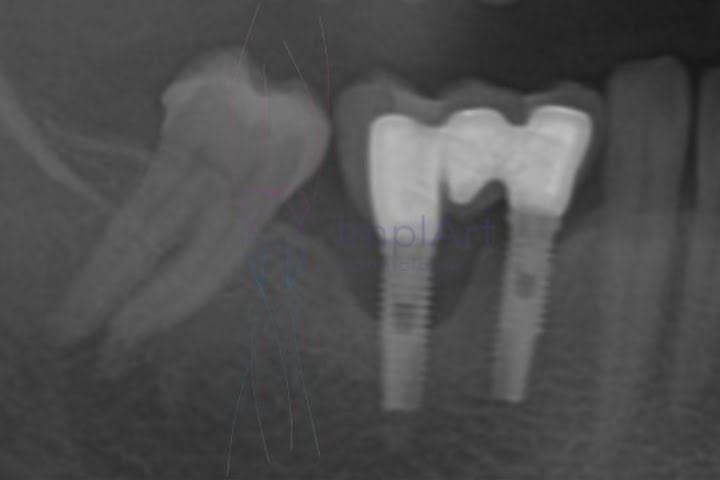

Os implantes dentários podem sofrer com doença periodontal (periimplantite), e ela ocorre na maioria das vezes por causa de uma higienização oral inadequada. Entenda a seguir.

A doença periodontal é uma doença crônica de origem bacteriana que manifesta uma série de condições inflamatórias que afetam os tecidos gengival e ósseo que torno dos dentes. Os implantes dentários com prótese fixa são indicados para suprir a ausência dentes, sendo capazes de devolver a estética e a capacidade mastigatória.

As bactérias presentes na placa acumulada na superfície dentária é a responsável pela inflamação dos tecidos. Inicialmente ela causa inflamação das gengivas (gengivite), em casos moderados há o surgimentos de bolsas periodontais, que é quando a gengiva perde aderência e adquire o formato de bolsa.

As bolsas periodontais abrem espaço para atividade bacteriana na região abaixo da gengiva, causando inflamação e deterioração progressiva do tecido ósseo responsável pela sustentação do implantes.

Essa condição quase sempre leva a mobilidade e perda do implante dentário. Vale ressaltar que a periimplantite (doença periodontal em implante) nem sempre é causada por problemas de higienização oral inadequada, portanto é essencial que o o paciente retorne ao consultório para avaliações periódicas dos implantes.